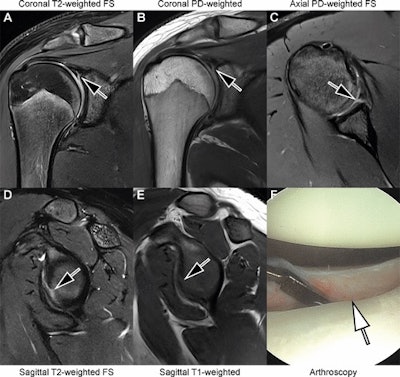

Images in an 18-year-old man with recurrent dislocations of the right shoulder. (A, B) Unenhanced coronal, (C) axial, and (D, E) sagittal deep learning super-resolution threefold parallel imaging -- accelerated turbo spin-echo MRI scans were obtained at 3-tesla field strength. (A) Coronal T2-weighted fat-suppressed (FS) and (B) coronal proton density (PD)-weighted MRI scans show a nondisplaced superior labral tear (arrows). (C) Axial proton density-weighted fat-suppressed, (D) sagittal T2-weighted fat-suppressed, and (E) sagittal T1-weighted MRI scans show continuation into a nondisplaced anteroinferior labral tear (arrows). All seven readers correctly diagnosed the arthroscopy-validated findings. (F) An arthroscopic photograph shows the anteroinferior labral tear (arrow). Image and caption courtesy of the RSNA.

Images in an 18-year-old man with recurrent dislocations of the right shoulder. (A, B) Unenhanced coronal, (C) axial, and (D, E) sagittal deep learning super-resolution threefold parallel imaging -- accelerated turbo spin-echo MRI scans were obtained at 3-tesla field strength. (A) Coronal T2-weighted fat-suppressed (FS) and (B) coronal proton density (PD)-weighted MRI scans show a nondisplaced superior labral tear (arrows). (C) Axial proton density-weighted fat-suppressed, (D) sagittal T2-weighted fat-suppressed, and (E) sagittal T1-weighted MRI scans show continuation into a nondisplaced anteroinferior labral tear (arrows). All seven readers correctly diagnosed the arthroscopy-validated findings. (F) An arthroscopic photograph shows the anteroinferior labral tear (arrow). Image and caption courtesy of the RSNA.

For instance, the scans allowed the readers to correctly categorize the supraspinatus-infraspinatus tendons as normal versus partial-thickness tear versus full-thickness tear with a sensitivity of 89%, a specificity of 90%, and an accuracy of 89%. They also achieved a sensitivity of 93%, a specificity of 73%, and an accuracy of 86% for diagnosing tears of the superior labrum.